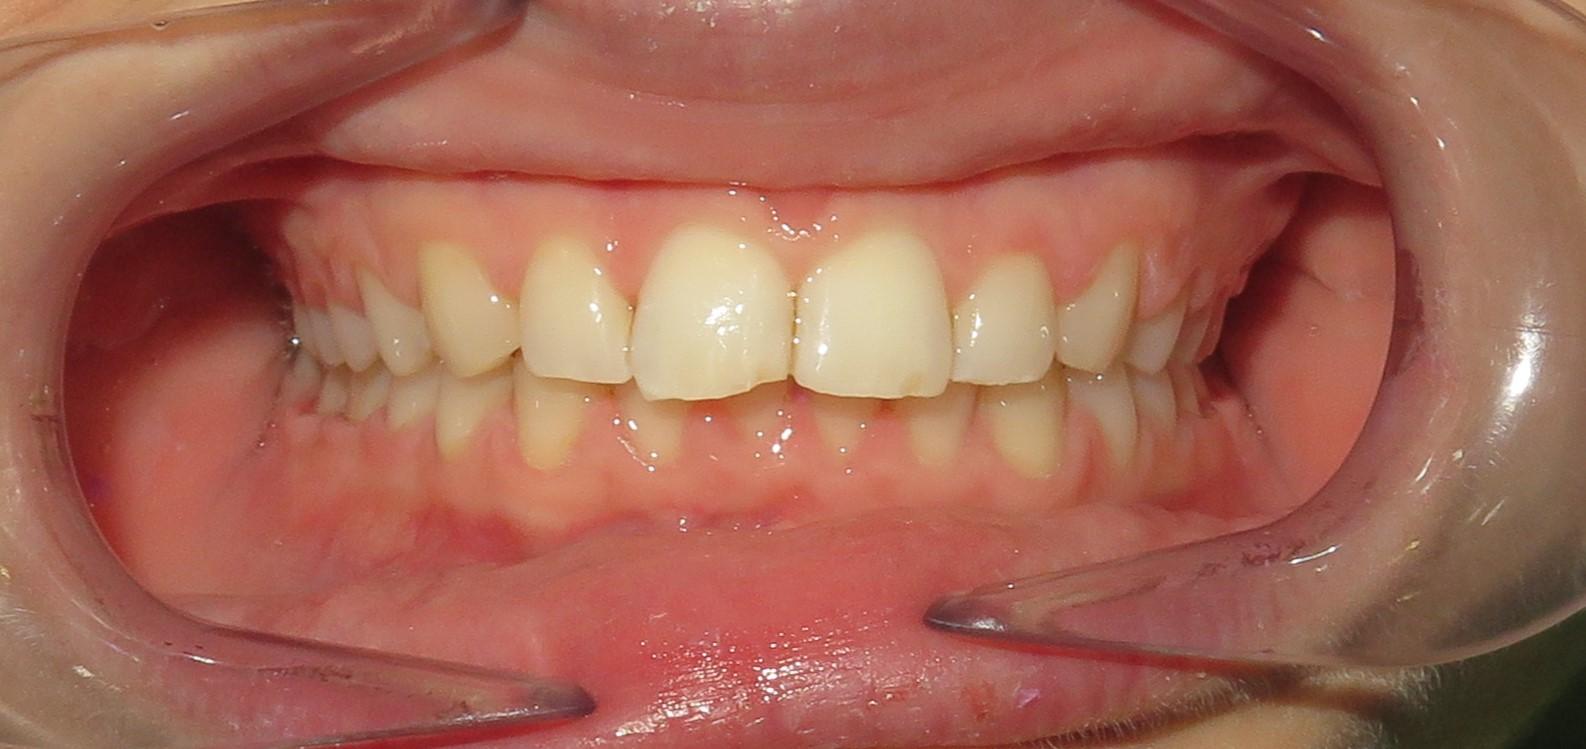

Leczenie aparatem stałym metalowym ligaturowym, które trwało 1,5 roku.

Głównym problemem był zgryz otwarty przedni, a także rotacje zębów oraz mała ekspozycja siekaczy w uśmiechu.

Pacjentka zgłosiła się do nas z takimi problemami, jak:

❌ zwężone łuki zębowe,

❌ tyłozgryz,

❌ głęboki zgryz,

❌ stłoczenia,

❌ zrotowane i starte zęby

Pod opieką Agnieszki Łukowicz, Master of Science Orthodontics została poddana zaawansowanemu leczeniu aparatem stałym ligaturowym, Dzięki czemu udało się osiągnąć znaczące zmiany:

✅poszerzenie luków zębowych,

✅korekta tyłozgryzu,

✅rozwiązanie stłoczenia,

✅odrotowanie zrotowanych zębów,

✅odbudowa startych zębów.

Efekt estetyczny został dopełniony przez wybielanie zębów i odbudowę kompozytową wykonaną przez dr Monikę Niewitecką.

Przedstawiamy piękny i zdrowy uśmiech naszej Pacjentki!